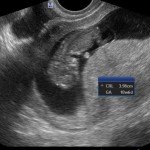

L’ecografia è una tecnica che consente di vedere gli organi del nostro corpo con l’utilizzo di onde sonore ad alta frequenza (ultrasuoni, non udibili dall’orecchio umano) che attraversano i tessuti. La sonda ecografica invia impulsi di onde sonore nel corpo. Quando le onde sonore arrivano al feto mandano degli echi: tali echi (o onde di ritorno) sono trasformati in immagini sul monitor dell’ecografo. Con l’ecografia è quindi possibile osservare in modo dettagliato il feto.

- Perché fare l’ecografia in gravidanza?

Le ragioni più comuni per cui si esegue una ecografia in gravidanza sono: determinare il numero degli embrioni o dei feti, visualizzare l’attività cardiaca fetale, determinare l’epoca di gravidanza, valutare l’anatomia e la crescita fetale, determinare la posizione del feto e della placenta

- Che cosa si vede con l’ecografia?

Nei primi mesi di gravidanza, con la misura della lunghezza del feto, è possibile valutare se lo sviluppo corrisponde all’epoca di gravidanza valutata in base alla data dell’ultima mestruazione, il numero dei feti e la presenza dell’attività cardiaca.

Dal secondo trimestre si misurano altre parti fetali, ed i valori di tali misure vengono confrontati con quelli delle curve di riferimento. Si può così valutare la normalità o meno della crescita fetale. Inoltre periodo si visualizzano la sede di inserzione placentare e la quantità di liquido amniotico.

- E’ possibile rilevare con l’ecografia anomalie fetali maggiori?

La possibilità di rilevare un’anomalia maggiore dipende dalla sua entità, dalla posizione del feto in utero, dalla quantità di liquido amniotico e dallo spessore della parete addominale materna; perciò è possibile che talune anomalie fetali possano non essere rilevate all’esame ecografico. Inoltre alcune malformazioni si manifestano tardivamente (al 7°- 9° mese) e perciò non sono visualizzabili in esami precoci. L’esperienza finora acquisita suggerisce che un esame ecografico routinario, non mirato, consente di identificare dal 30 al 70% delle malformazioni maggiori. Non è compito dell’ecografia la rilevazione delle cosiddette anomalie minori (Linee Guida SIEOG 2006).

- L’ecografia è innocua per il feto?

Gli ultrasuoni sono utilizzati nella pratica ostetrica da oltre 40 anni e non sono stati riportati effetti dannosi, anche a lungo termine, sul feto. Per tale ragione, con le procedure oggi adottate, l’uso diagnostico dell’ecografia è ritenuto esente da rischi. Ovviamente, come in tutte le cose, è bene non eccedere oltre la necessità facendo frequenti esami non necessari.

A fianco alla più tradizionale ecografia eseguita per via transaddominale, risulta particolarmente utile nell’esame ecografico ostetrico e ginecologico la via di accesso transvaginale.

Con questa metodica, utilizzando delle sonde ecografiche appositamente predisposte (per forma e dimensione, e per frequenza di emissione degli ultrasuoni) è possibile controllare la gravidanza nel primo trimestre con una qualità e definizione d’ immagine nettamente superiori a quanto possibile per via transaddominale.

Per eseguire l’ecografia transvaginale non è richiesta la vescica piena, diversamente rispetto a quanto richiesto per l’ecografia transaddominale. L’approccio transvaginale consente di aggirare l’ostacolo dovuto ad un aumentato spessore della parete addominale (obesità). In questi casi infatti la qualità d’ immagine in caso di ecografia transaddominale viene fortemente penalizzata dall’eccessivo spessore del pannicolo adiposo addominale.

Con l’ecografia transvaginale è possibile vedere dopo circa 3 settimane dal concepimento la camera gestazionale nella cavità uterina. Successivamente è possibile visualizzare l’embrione (3-5 mm.) a circa 6 settimane dall’ultima mestruazione (4 settimane dal concepimento) ed a questo periodo è già visibile l’attività cardiaca fetale Anche i primi dettagli sulla morfologia fetale (polo cefalico, abbozzi degli arti) sono visualizzabili più precocemente con l’ecografia transvaginale, risultando essi visibili intorno a 8-9 settimane.

Con l’ecografia dei primi mesi di gravidanza, si può anche valutare la normalità dell’utero (eventuale presenza di fibromi già preesistenti alla gravidanza) e delle ovaie.

Con il finire del primo trimestre per il controllo ecografico di routine della gravidanza la via transvaginale viene poi sostituita dalla via transaddominale.

Successivamente può risultare utile il ricorso all’ ecografia transvaginale nei casi in cui si sospettino delle modificazioni precoci (raccorciamento) del collo dell’utero, come potrebbe verificarsi nei casi di minaccia d’ aborto o di parto pretermine.

In questi casi infatti è possibile con l’ ecografia misurare con precisione la lunghezza del collo uterino. In questi casi inoltre l’ ecografia può anche evidenziare un’ iniziale dilatazione dell’ orifizio uterino interno. Tali modificazioni del collo dell’ utero, valutabili con accuratezza solo con l’ ecografia transvaginale, hanno una grande importanza nel considerare un eventuale rischio di parto pre-termine.